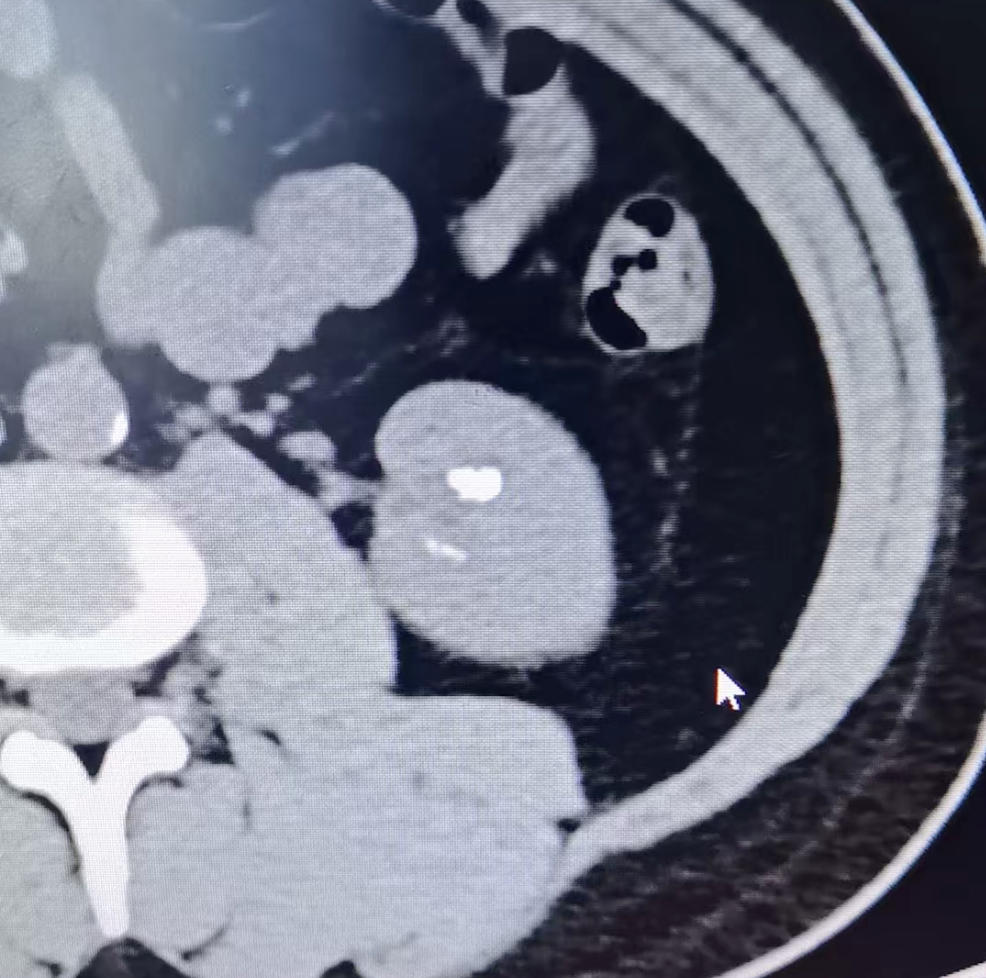

1.诊断方法:医生通常会结合症状,进行尿常规、B超、CT等检查来确诊结石的大小、位置和数量。